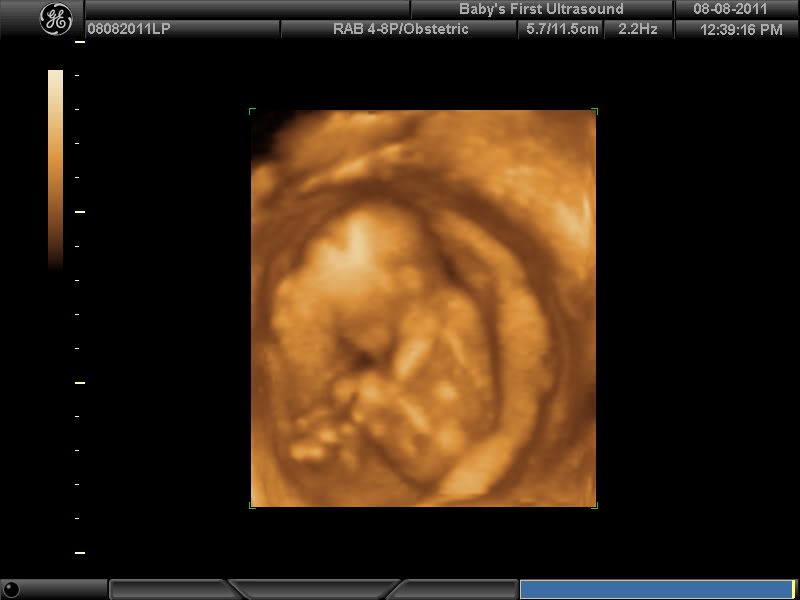

Now Introducing Lawson (PIP)

Wow Storm...it must be so exciting to see him growing all nice and baby-like :-)

I didn't show the legs open shot LOL I just felt weird about that. But I will say he is 100% boy!

Thanks for all the support ladies. I am so in love!